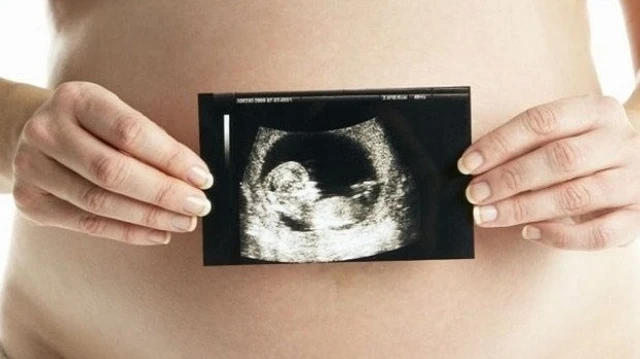

Trong quá trình thai kỳ, việc thực hiện các cuộc khám thai theo lịch trình do bác sĩ chỉ định là rất quan trọng để đảm bảo sức khỏe của cả mẹ và thai nhi. Một trong những yếu tố mà nhiều người mẹ quan tâm đặc biệt là độ mờ da gáy, vì chỉ số này có thể phản ánh nguy cơ mắc phải hội chứng Down cho thai nhi. Vậy, mức độ mờ da gáy 1.8mm có bình thường không nhỉ?